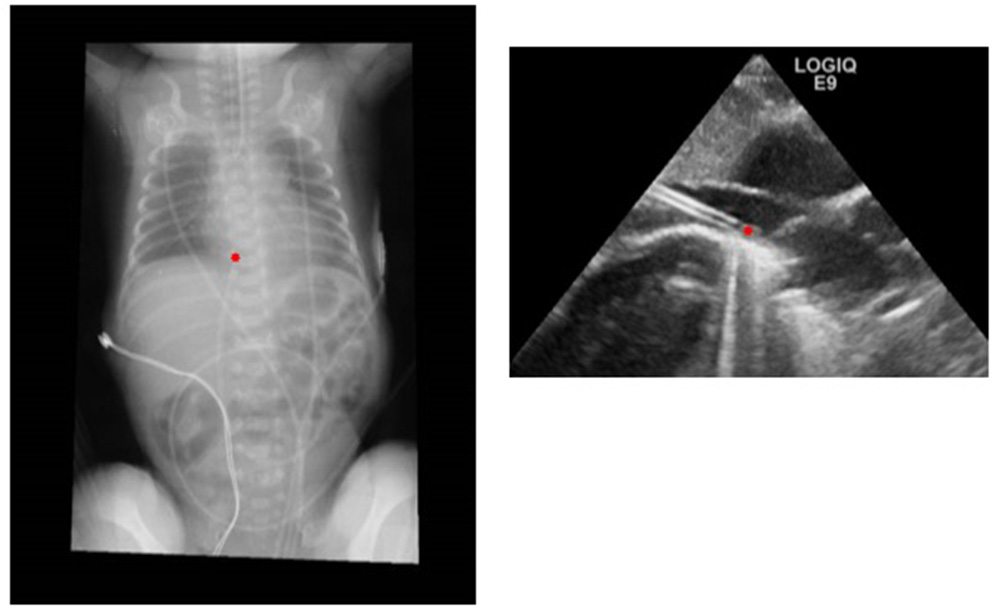

The newest and most interesting development in UVC insertion is indeed the introduction of ultrasound-based methods for tip navigation and tip location. The use of point-of-care ultrasound (POCUS) to visualize umbilical catheters during the procedure is rapidly spreading among neonatologists (11, 12, 42–44) (Figure 2).

Figure 2

Comparison of radiographic and ultrasound images of a correctly positioned UVC.